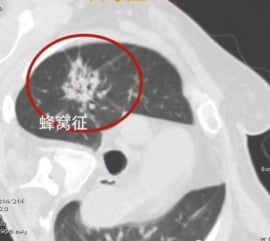

八、蜂窝征:黏液样癌的特殊表现

蜂窝征通常表现为实性或倾向于实性密度的病灶,其内部密布着众多微小的空泡,整体呈现出复杂的蜂窝状图案。在疾病早期,这类病灶常被误判为炎症。然而,随着研究深入,我们认识到这类病灶绝大多数具有恶性潜能,并可能经历了从磨玻璃样改变向更致密实性病灶的演变。当部分区域尚未完全密实,呈现出类似蜂窝的外观时,这往往是黏液样癌可能性较高的强烈信号。对于此类具有独特影像学特征的肺部结节,应保持高度警惕。